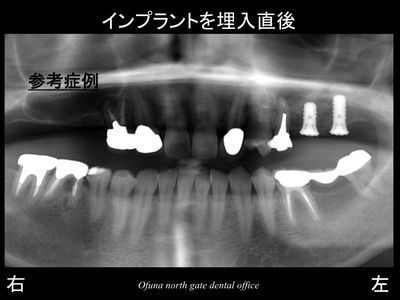

以下がソケットリフト法 でインプラントを埋入した直後です。

ソケットリフト法 の状態を拡大して見てみましょう!

以下の丸で囲んだ部位を拡大します。

拡大したところです。